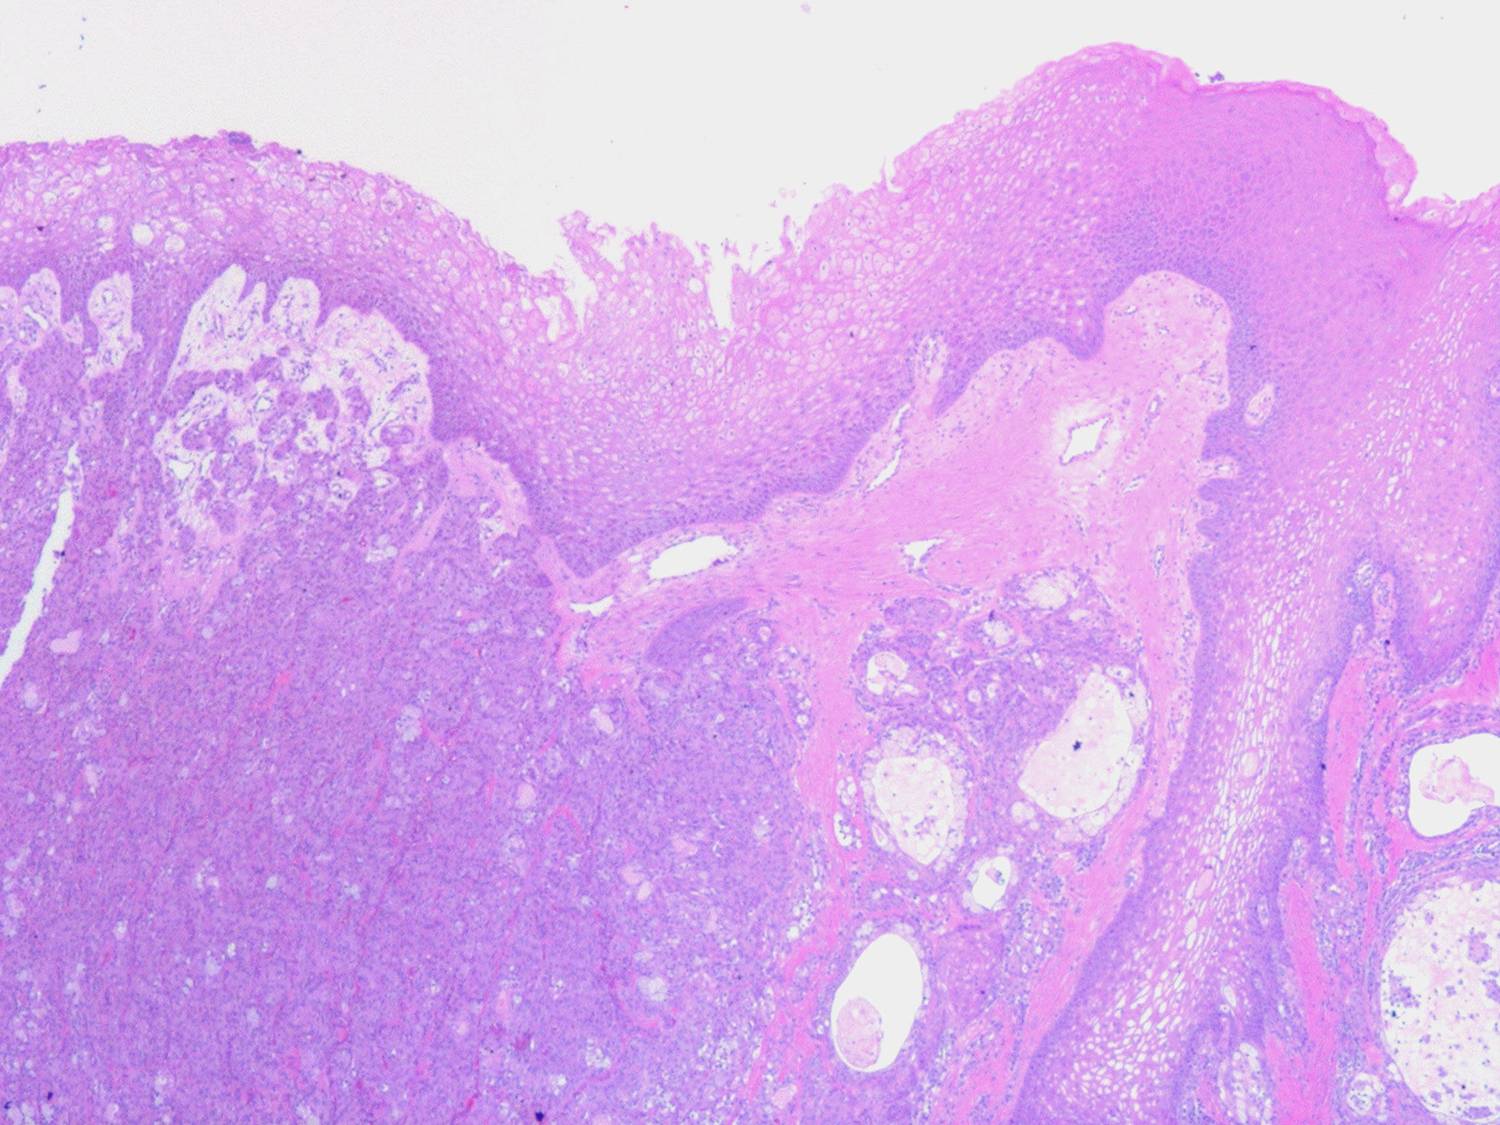

Mucoepidermoid carcinoma =الكارسينوما المخاطية البشروانية